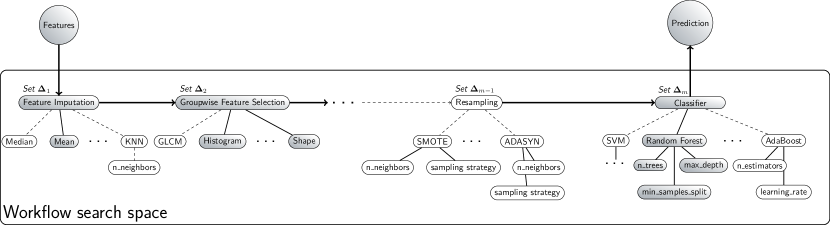

A schematic overview of the algorithm and hyperparameter search space is shown in Figure 1. The resulting framework is coined WORC (Workflow for Optimal Radiomics Classification). Including new algorithms and hyperparameters in this reformulation is straight-forward, as these can simply be added to and , respectively.

In order to formulate radiomics as a CASH problem, the workflow needs to be modular and consist of standardized components. In this way, for each component, a set of algorithms and hyperparameters can be defined. We therefore split the radiomics workflow into the following components: image and segmentation preprocessing, feature extraction, feature and sample preprocessing, and machine learning. An overview of the default included components, algorithms, and associated hyperparameters in the WORC framework is provided in Table 1. Details on the included algorithms and their associated hyperparameters are given in .1.